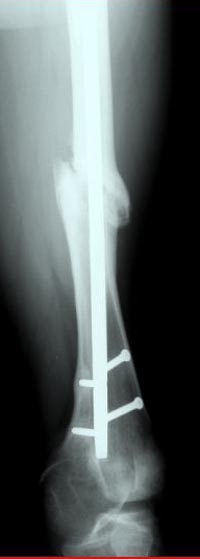

Из истории болезни: два года назад проперирован по поводу 3А открытого перелома бедра, травма на работе в результате "стена упала на него". Сопутствующая травма: Закрытая травма черепа, перелом голеностопного сустава (прооперериван) и перелом плеча (консервативное лечение)

Лечение бедра - ургентное оперативное лечение антеградным с минимально рассверливанием, фиксацией с минимальным диаметром штифта и плюс irrigation and debridment и с закрытием поперечной до 10 см раны на уровне перелома в день поступления.

Снимки представлены: 1 мес; 3 мес; 1 год; 2 года, предоперационные и ротационная КТ грамма

Деформация:

Вальгус- 17 градусов

Рекурватум 5 градусов

Укорочение 2.5см

Ротационно 22 градусов внутренная

Смещение диафиза по поперечнику 75%

Аппарат Илизарова= Taylor spatial frame

Операцию провели в два этапа, сперва удалили штифт, рассверливание римером на пару мм большего диаметра, определение чувствительности на анаэробную и аэробную культуру (где исследования показали негативный результат чувствительности), через дней десять - начали аппаратную фиксацию.